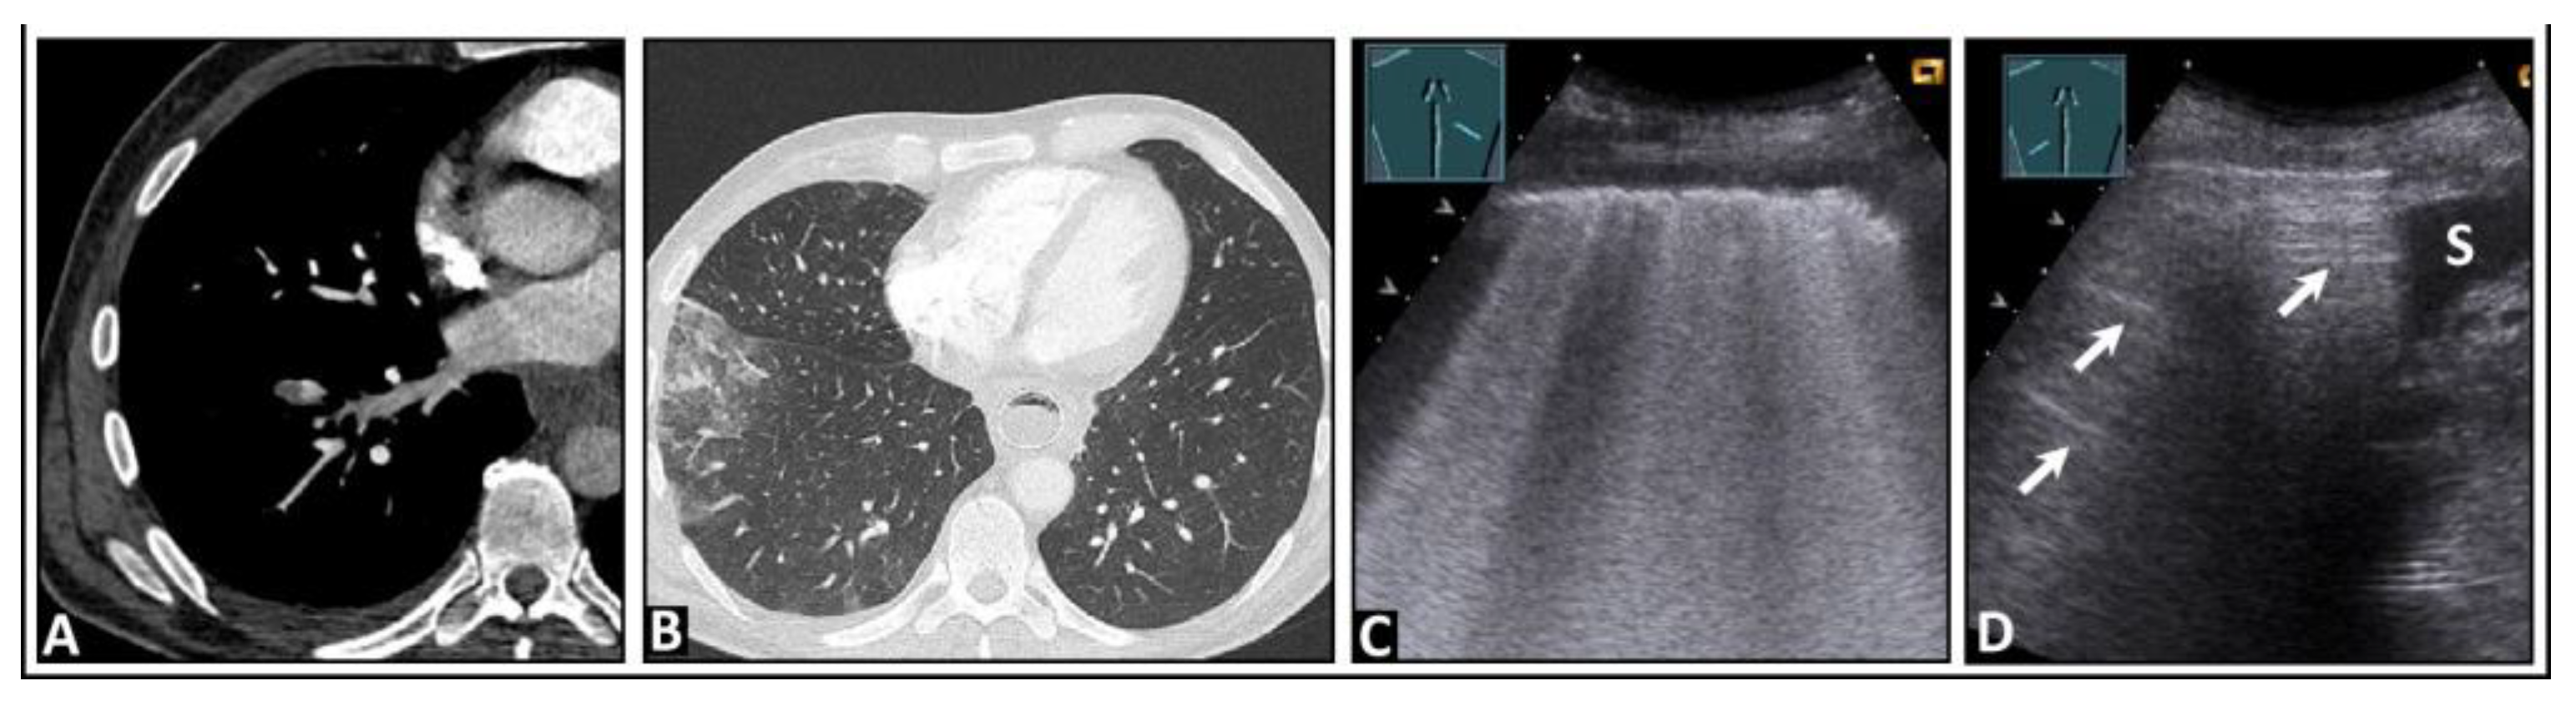

7. Other Pathologic Situations

8. Pleural Artifacts with Simultaneous Presence of Consolidation